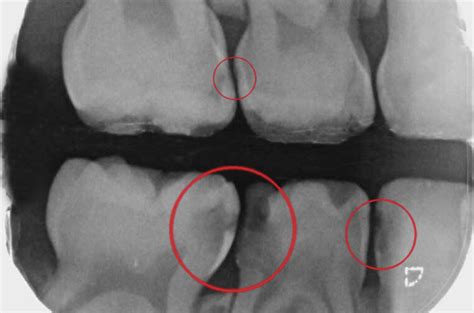

Las lesiones situadas en las zonas interproximales tienen un inconveniente y es que no se ven hasta que no se fractura todo el reborde marginal, de manera que suelen ser diagnosticadas por las radiografías. Radiográficamente las lesiones de caries son evaluadas en las superficies interproximales mediante el uso de la radiografía de aleta mordida. El propósito de esta radiografía es detectar lesiones ocultas al examen clínico, como sucede en las superficies interdentales. Estas lesiones cariosas tienen que ser diagnosticadas antes que se afecte el reborde marginal, porque se tratará de lesiones muy profundas. Son muy importantes las revisiones periódicas en el dentista para poder detectar las caries interproximales de forma precoz. Será el especialista quien, mediante una radiografía, pueda hacer un diagnóstico y aplicar el tratamiento para las caries interproximales más adecuado.